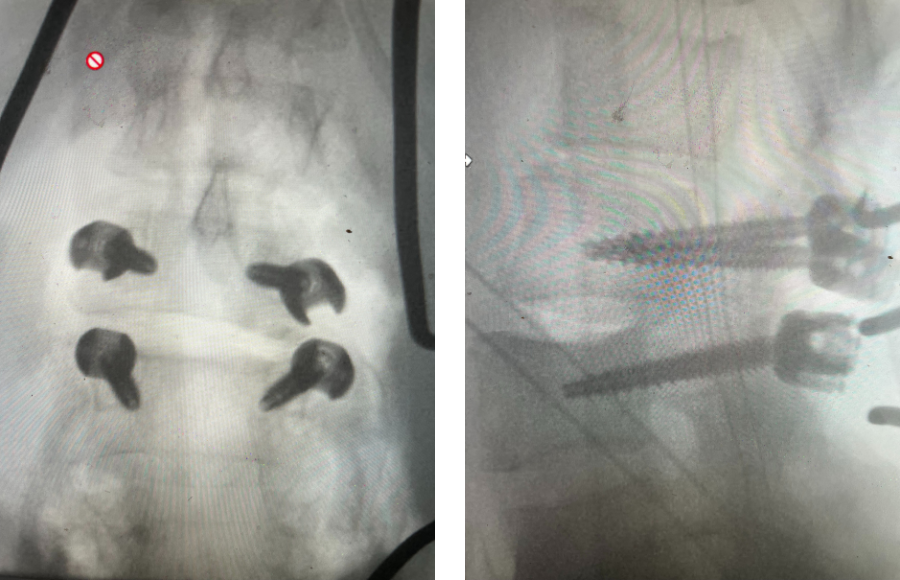

Here is a dramatic example of a patient who had prior laminectomy and fusion surgery four years earlier, and now presents with low back pain with severe burning pain in her right lower extremity pain. She did not respond to epidural steroids. She had a prior L3-S1 laminectomy, and an L3-5 instrumented fusion. A current MRI (Fig 4) demonstrated severe L2-3 next segment stenosis due the development of massively hypertrophied or enlarged L2-3 joint complexes. There was also a grade 1 retrolisthesis of L2 on L3 with a large anterior disc osteophyte complex. The configuration of the stenosis was worse in the right lateral recess secondary to the anterior osteophyte and more right-sided facet compression of the thecal sac, correlating with the patient’s right-sided symptoms. When the anatomy correlates with the patient’s symptoms that is the best set up for success. It was decided to offer a revision surgery to the patient, who agreed.

Revision surgery is more involved than primary surgery. In order to start decompressing this large complex, you must develop a plane; you have to find the edge of sometimes a remnant of a lamina or the lamina that can be buried in scar. You must carefully dissect the edge with a sharp upbiting curette and then either using a sharp Leksell to start removing this lamina or use a fine Kerrison to widen the plane and exposure and begin to expose the normal ligamentum above. In this case it was critical to expose and decompress the L3 nerve roots bilaterally. What is quite helpful is finding the inferior edge of the L2 facets. Then one must lift up the inferior L2 process up with a curette and simultaneously insert a Kerrison into joint space and remove the whole facet process. This is a great move because it allows access to the plane between the superior facet and the descending nerve root and a starting point to fully decompress the nerve root. Because of scarring there often is not a clear plane in order to accomplish the decompression. Care is taken to make sure there is a clear separation between edge of bone and dura during the process of inserting a Kerrison edge. The important part of this is feeling your opening and actually using your Kerrison as a dissecting tool once an edge has been established to perform a foraminotomy. We were able to remove the inferior L2 facet process with impunity as we knew we were performing an instrumented fusion to L2. The patient’s had a prior L3-5 instrumented fusion which upon exploration was solidly fused. It was decided to remove her prior hardware as it served its purpose and add a short segment from L2-3 (Fig 5). Patient did well after her surgery with relief of her right leg pain.

Fig 5: intraoperative fluoroscopic images demonstrating L2-3 screw placement.